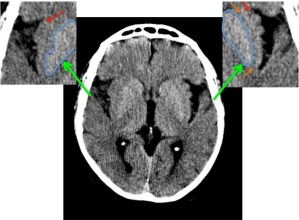

CASO 2:

Paciente con alteraciones del habla y disminución de la fuerza del brazo izquierdo. Ictus previo hace 4 años.

ASPECTS: Territorio M1 + Lenticular derecho = 10 – 2 = 8 puntos.